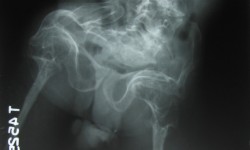

INFANTILE OSTEOPETROSIS By Admin | October 1, 2013 - 4:01 pm | Musculoskeletal, Skeletal Dysplasias Leave a comment FIG. 1 Skull lateral Fig.2 T>L Spine lateral Fig.3 Pelvis A.P with hip and femurs